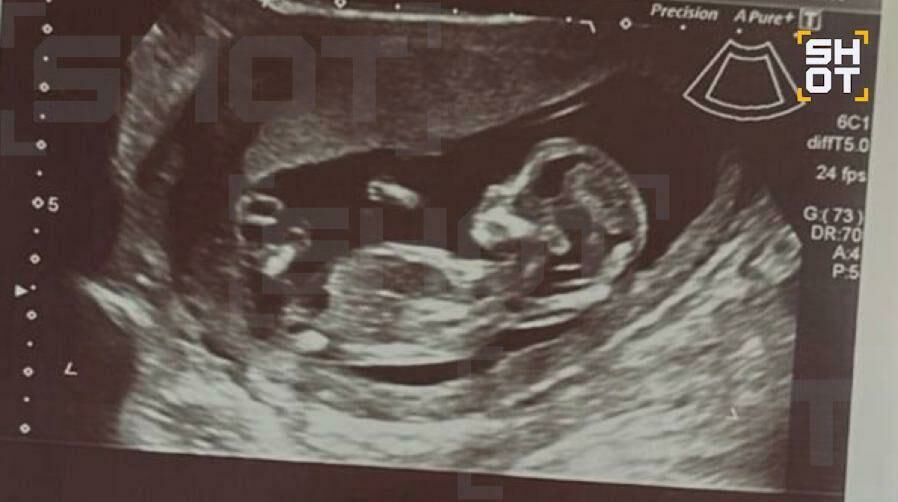

Выяснилось, что во время операции девушка уже была на пятой неделе беременности: ребенок пережил наркоз и воздействие множества лекарственных препаратов в восстановительный период. Эксперты предупреждают, что на пятом месяце развития формируются важнейшие органы, и вмешательство могло отрицательно сказаться на этом этапе.

Telegram-канал SHOT сообщает, что сейчас девушка регулярно посещает врача, беременность протекает нормально.